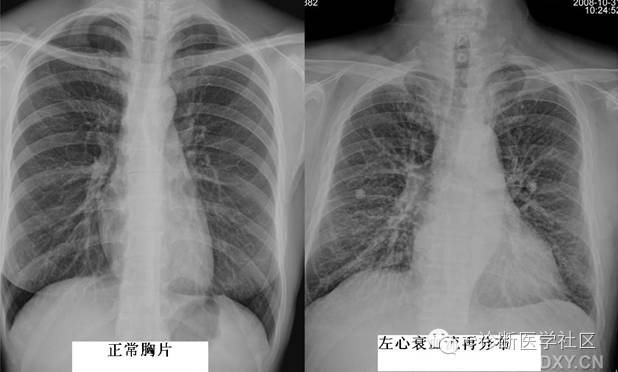

2血管性肺纹理增强

主要由肺充血和肺淤血引起肺充血多见于具有由左向右分流的先天性心脏病,如房间隔缺损、室间隔缺损等。这是由于肺血流量增加(动脉充血)使肺动脉扩张之故,表现为肺纹理较粗大,边缘较清楚,从肺门向肺内保持血管的特征。肺淤血多见于左心衰竭后肺静脉压力升高所致之肺静脉的扩张,表现为肺纹理增根、增多,边缘模糊,以两上肺野明显,肺野透过度减低。